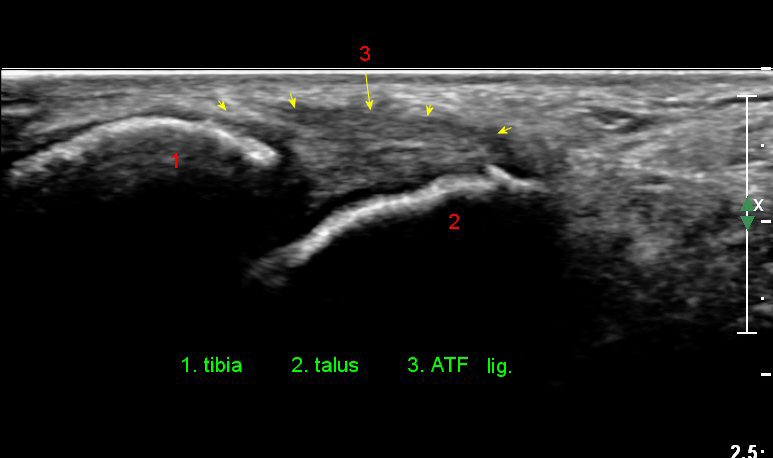

Àü°ÅºñÀδë Á¾´Ü¸é°Ë»ç¿¡¼­ ¾È´ë ºñ°ñ ºÎÂøºÎÀÇ Àú¿¡ÄÚ ºÎÁ¾°ú ºÎºÐÆÄ¿­ÀÌ °üÂûµÈ´Ù(»çÁø 4).

Àü°ÅºñÀδë Á¾´Ü¸é°Ë»ç¿¡¼­  Àú¿¡ÄÚ ºÎÁ¾ÀÌ °¨¼ÒÇϰí ÀδëÀÇ ¿¡ÄÚ°¡ Áõ°¡µÇ¾ú´Ù(»çÁø 2, 3, 4).